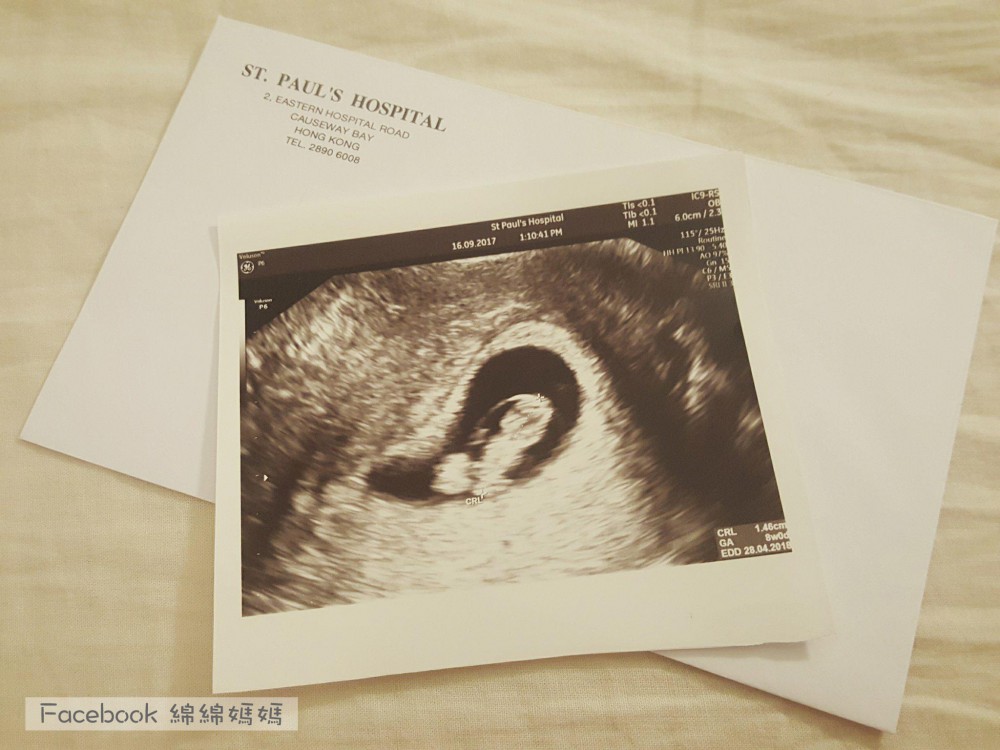

16 Sep 2017

本身諗住到10W先去搵私家照閃閃,

17 Sep 2017

終於可以見到 St. Paul 謝醫生, 老公陪住我入去檢查, 當時醫生有幫我嘗試照肚超,但可能仲細,睇唔清楚BB,